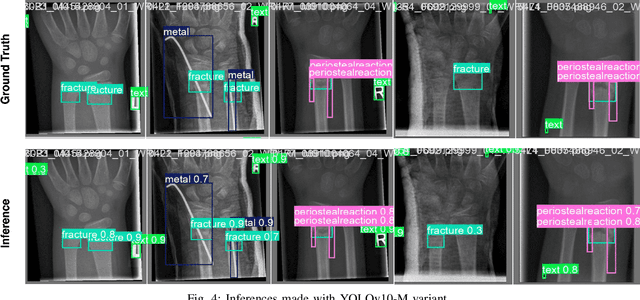

Abstract:Wrist fractures are highly prevalent among children and can significantly impact their daily activities, such as attending school, participating in sports, and performing basic self-care tasks. If not treated properly, these fractures can result in chronic pain, reduced wrist functionality, and other long-term complications. Recently, advancements in object detection have shown promise in enhancing fracture detection, with systems achieving accuracy comparable to, or even surpassing, that of human radiologists. The YOLO series, in particular, has demonstrated notable success in this domain. This study is the first to provide a thorough evaluation of various YOLOv10 variants to assess their performance in detecting pediatric wrist fractures using the GRAZPEDWRI-DX dataset. It investigates how changes in model complexity, scaling the architecture, and implementing a dual-label assignment strategy can enhance detection performance. Experimental results indicate that our trained model achieved mean average precision (mAP@50-95) of 51.9\% surpassing the current YOLOv9 benchmark of 43.3\% on this dataset. This represents an improvement of 8.6\%. The implementation code is publicly available at https://github.com/ammarlodhi255/YOLOv10-Fracture-Detection